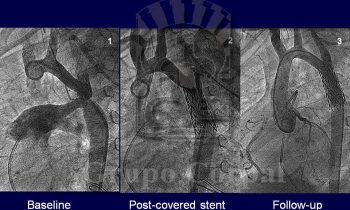

Paciente diagnosticado de Hipertensión Arterial con Coartación de Aorta severa

Imágenes mes de octubre 2017, paciente de 50 años con Coartación de Aorta severa asociada a un aneurisma fusiforme de la aorta descendente post-coartación. Las Coartaciones de Aorta severas que son diagnosticadas en la...